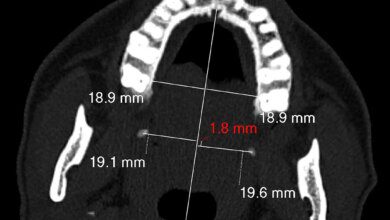

وباشرت الكوادر الطبية تدخلاً جراحيًا طارئًا لاستكشاف الصدر والقلب، حيث تبين وجود إصابة نافذة بطول 5 سم في عضلة البطين الأيسر، وتهتك في الرئة اليسرى، بالإضافة إلى كسر في أحد الأضلاع. وقد نجح الفريق في السيطرة على النزيف، وإصلاح الأعضاء المصابة، وتثبيت الكسر باستخدام شريحة من التيتانيوم.